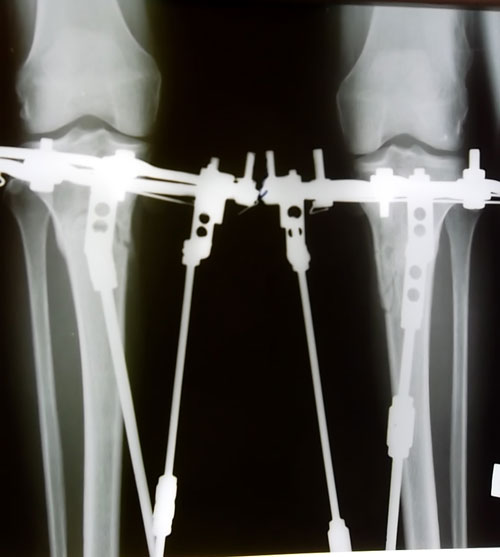

рентгеновские снимки в день снятия аппаратов Илизарова - Онипко.Вот такая МОЩНАЯ костная мозоль бывает у женщин в 49 лет через 3 месяца после операции. (в день снятия аппаратов)

Пациентка Надежда.

Дата операции 26.06.2012г.

Дата снятия 01.10.2012г.

Срок лечения 95 дней.